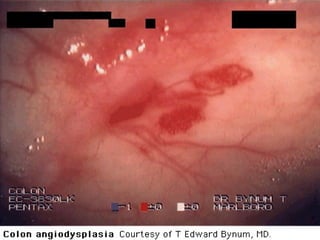

Angiodisplasia

• Son vasos submucosos dilatados, las paredes de estos

vasos carecen de fibras musculares.

• Es poco común (Incidencia < 1%).

• Incidencia aumenta con edad.

• 20 a 30% de todos los casos de hematoquezia.

• Puede ser una de las principales causas de sangrado en

>65 años: divertículos, angiodisplasia y cáncer.

• El sangrado es episódico y autolimitado.

• Suele estar asociada a IRC, Von Willebrandt, cirrosis ?.

• Mas común en ciego y colon ascendente.

Angiodisplasia • Son vasossubmucosos dilatados, las paredes de estos vasos carecen de fibras musculares. • Es poco común (Incidencia < 1%). • Incidencia aumenta con edad. • 20 a 30% de todos los casos de hematoquezia. • Puede ser una de las principales causas de sangrado en >65 años: divertículos, angiodisplasia y cáncer. • El sangrado es episódico y autolimitado. • Suele estar asociada a IRC, Von Willebrandt, cirrosis ?. • Mas común en ciego y colon ascendente.